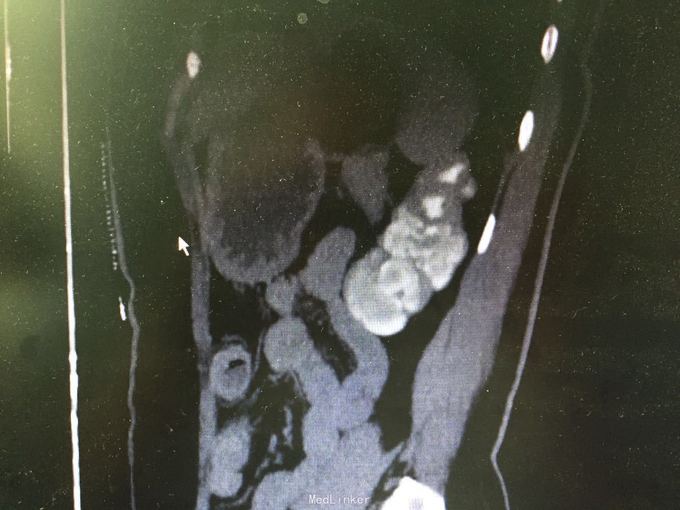

体检发现左肾萎缩11天 当地医院体检发现左肾萎缩,否认盗汗,发热。 2006年因盆腔结核住院治疗,自述规律抗结核治疗,具体不详。

查体:无殊,无阳性体征。 辅助检查:CTU:左肾萎缩,考虑肾结核自截肾。 胸部CT 右肺少量纤维化灶伴局部胸膜粘连改变。